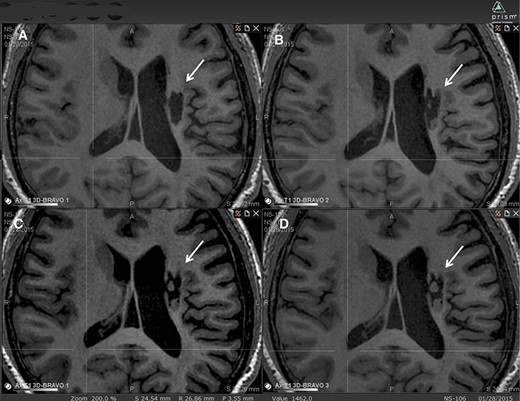

在6個月的隨訪中,所有9名受試者均觀察到新組織,源自腦軟化梗塞腔。該腔內組織外觀具有以下特征:短期活力(術后第一次MRI與基線相比的組織外觀)—9例中有9例;生長(術后至少兩次MRI中新組織增加)—6例中有6例;穩定(術后至少兩次MRI中新組織無變化;即生長平臺期,最長為24個月)—6例中有5例;無法獲得24個月后的長期活力。圖2顯示了腔內組織生長的縱向MRI示例。9名受試者的梗塞腔內這種無關組織的存在都很明顯(圖3)

圖2:腔內組織生長的縱向MRI示例。

圖中顯示了B組 (#106) 受試者在T1MRI上隨時間的變化。

(A):基線時,(B) 6個月隨訪時,(C) 12個月隨訪時,(D) 24個月隨訪時。箭頭表示梗塞腔。

可以看到兩個組織團塊,在基線時不存在,推測是來自植入的NSI-566,隨著時間的推移,它們似乎慢慢填滿了腔體。